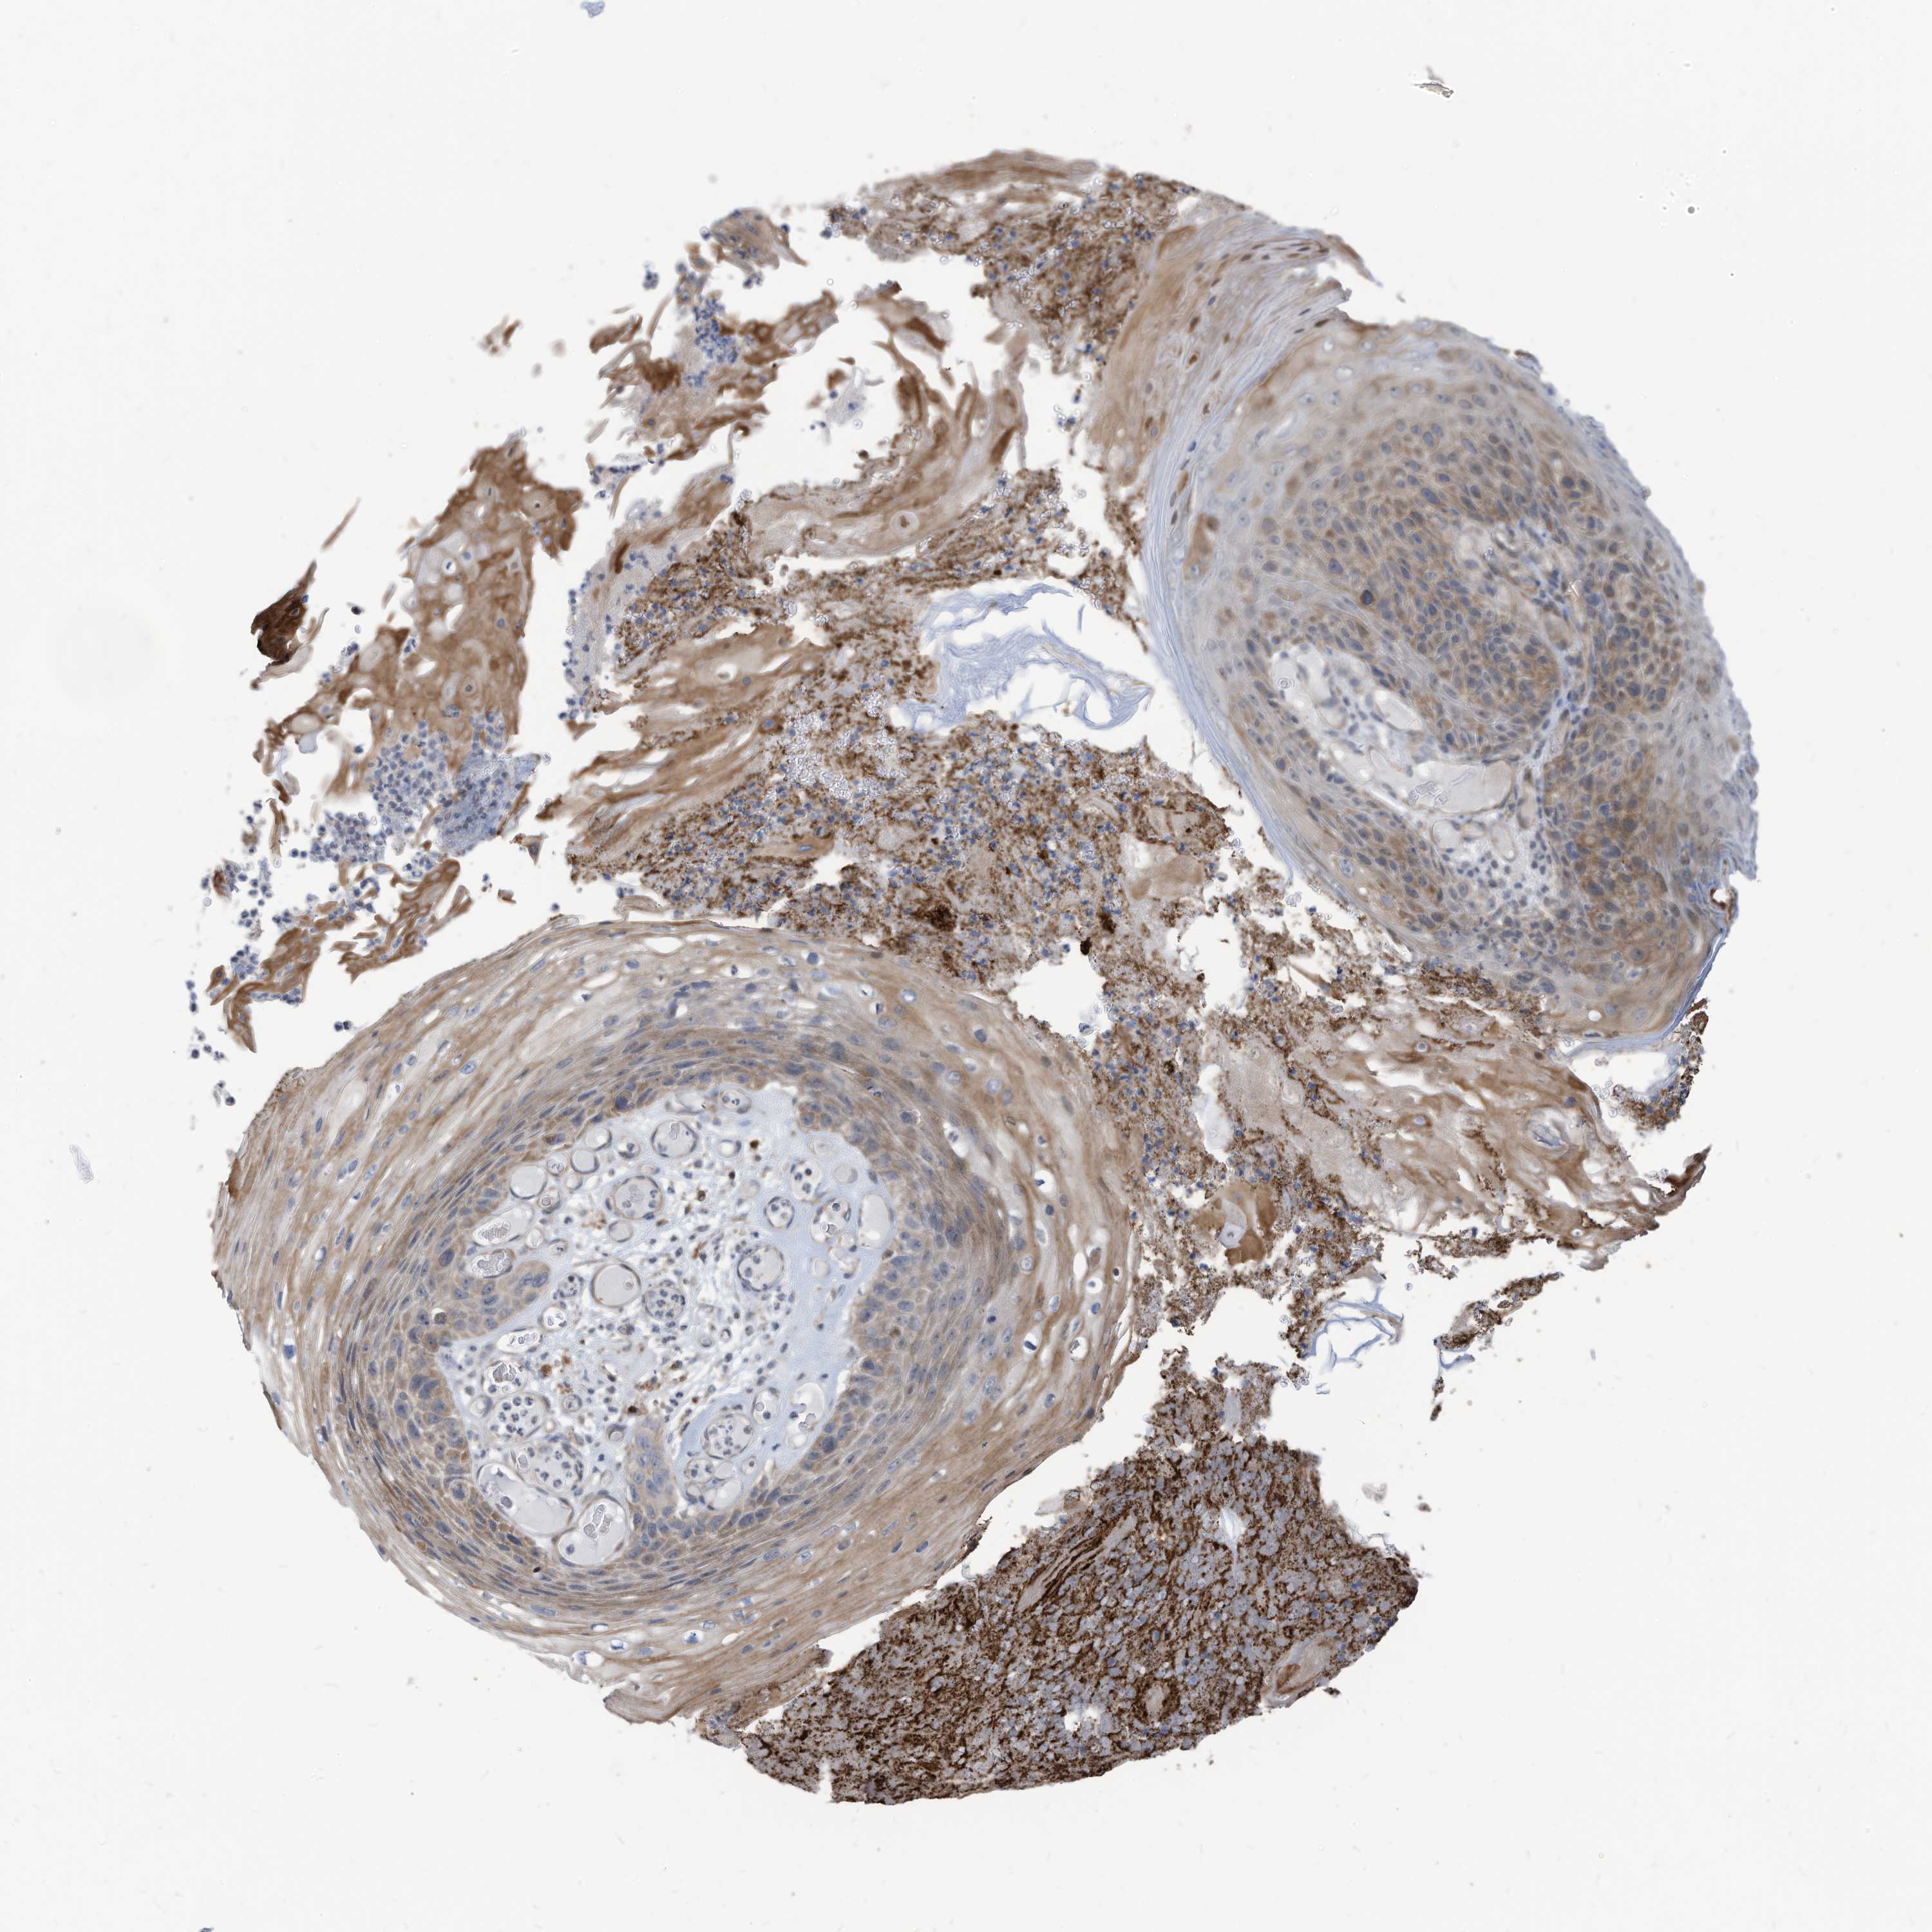

SKIN CANCER - Protein expressioni

A mouse-over function shows sample information and annotation data. Click on an image to view it in a full screen mode. Samples can be filtered based on level of antibody staining by selecting one or several of the following categories: high, medium, low and not detected. The assay and annotation is described here.

Antibody staining in the annotated cell types in the current human tissue is reported as not detected, low, medium, or high, based on conventional immunohistochemistry profiling in selected tissues. This score is based on the combination of the staining intensity and fraction of stained cells.

Each image is clickable and will lead to virtual microscopy that enables deeper exploration of all samples and also displays staining intensity scores, fraction scores and subcellular localization as well as patient and tissue information for each sample.

Antibody HPA032078

Staining

High

Medium

Low

Not detected

Intensity

Strong

Moderate

Weak

Negative

Quantity

>75%

75%-25%

<25%

None

Location

Nuclear

Cytoplasmic/membranous

Cytoplasmic/membranous,nuclear

Squamous cell carcinoma, metastatic, NOS